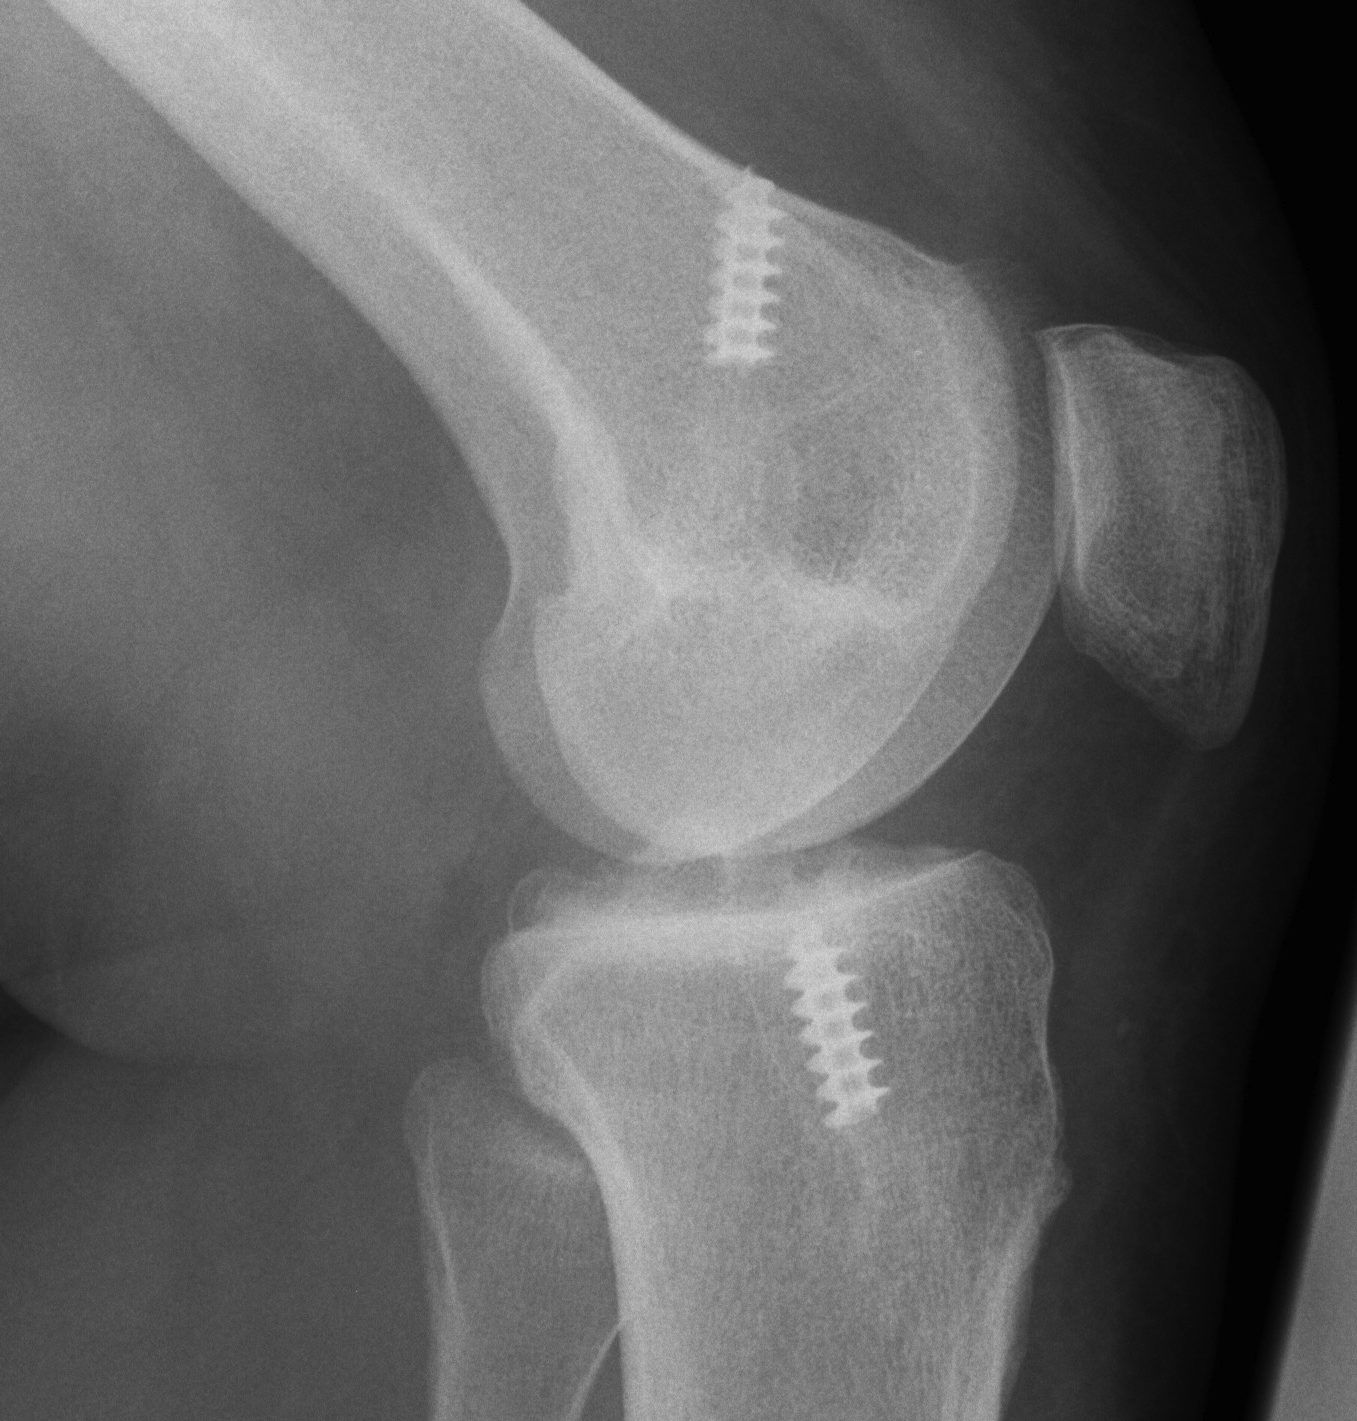

Xray

AP and Lateral

- assess tunnel placement

- Assess metal work

- types of fixation

- metal v plastic

Revision ACL Graft Placed posterior to old femoral tunnelRevision ACL New Posterior Femoral Tunnel